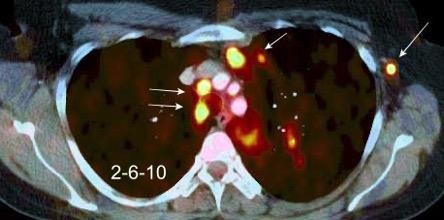

Masa axilar izquierda y derrame pleural derecho. Implantes pleurales, paraespinales . Ganglios en mamaria interna. Linfoma B difuso

Jaffe ES. Diagnosis and Classification of Lymphoma: Impact of Technical Advances.

2005. Masa pulmonar.

Linfoma NH de cél. B. Invasión Transtorácica.

Afectación axilar